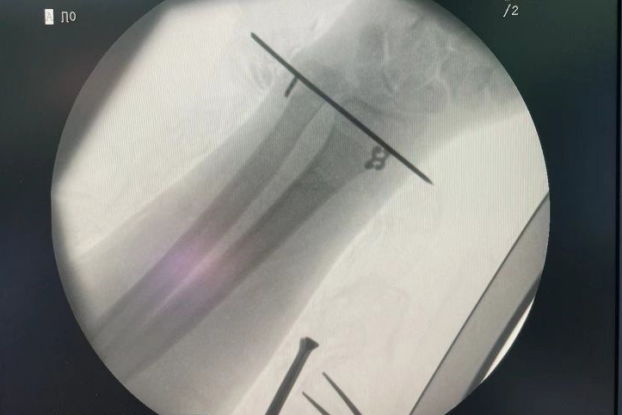

手術治療:彈性固定

帶孔導針穿過尺骨和橈骨,將牽引線放入尾孔導針后拉出;

將橈骨端縫線在可調節鈦板線圈系一單節;

牽引縫線撤出后將可調節鈦板線圈放入蝶形板線槽內;

收緊可調鈦板,使可調節鈦板、蝶形板分別緊貼尺骨及橈骨;

打結固定,剪斷多余縫線。

術后照片